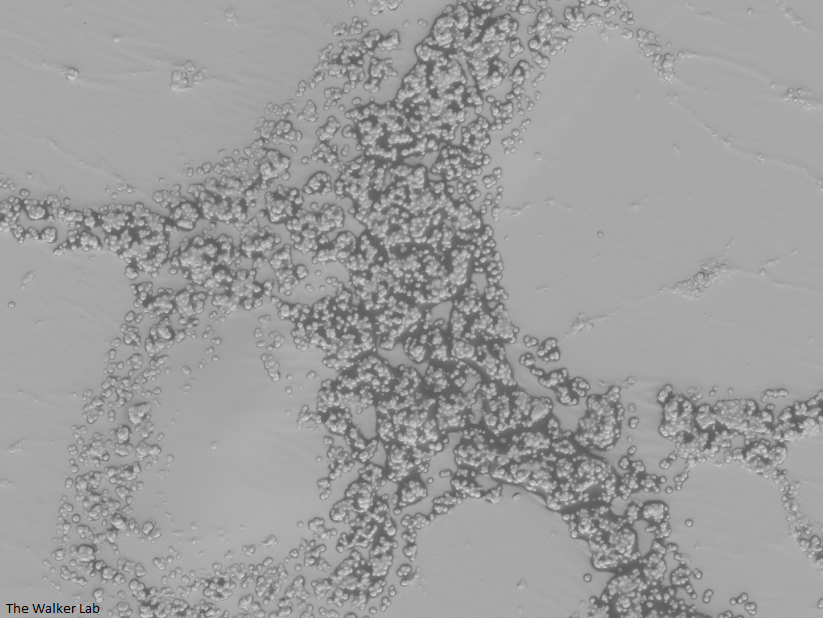

SEM Images of Mouse Catheters

Silicone urinary catheters have smooth surfaces, while latex urinary catheter surfaces are rough. Regardless of the catheter material, deposition of host inflammatory factors alters the surface and facilitates infection by atypical pathogens.

Latex Catheter Surface

Urinary catheters render people susceptible to atypical uropathogens. We use the atypical uropathogen, methicillin-resistant Staphylococcus aureus (MRSA), to study the catheter-host-pathogen interactions that facilitate disease.

The host inflammation response to the catheter recruits immune cells and wound healing proteins which are deposited on the catheter surface. Atypical pathogens can use these host factors to adhere to the catheter's large surface and create biofilm. Colonization of catheters occurs quicker than expected and develops even in the presence of prophylactic antibiotic therapy. MRSA is just one of the uropathogens that can attach to the altered urinary catheter surface. One host factor deposited on the catheter surface is fibrinogen. We recently discovered that MRSA binds fibrinogen to attach to the catheter surface and form biofilm, which increases antibiotic recalcitrance. Our future studies aim to develop new non-antibiotic strategies that interfere with those interactions to prevent or treat CAUTIs.